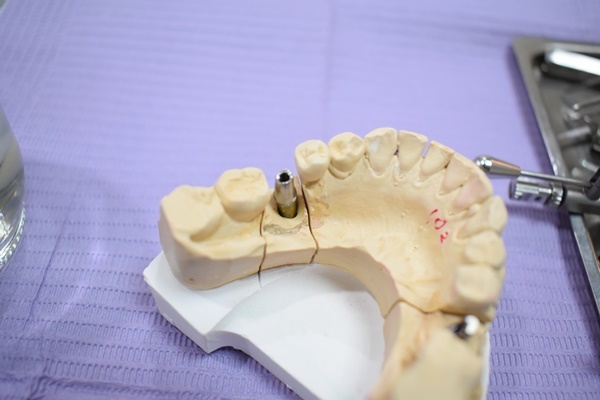

重建植牙並沒有想像中簡單,上個月讓醫生幫忙取出人工牙根後,當日醫師就替媽媽將傷口填入骨粉做縫合,填入骨粉用意是為了幫助日後植牙重建時牙根可以穩固,牙骨扎實才能牢牢將植體包覆不會鬆動,邏輯上就有點像是種樹般需要有大量泥土來掩蓋樹根一樣,這樣風吹日曬樹木才不會倒塌,種植牙齒也是一樣,骨質密度夠人工植牙使用年限才會久遠。

補骨粉之後兩週護士會先安排到院回診檢查傷口情況,取出之前種的植牙,手術過程雖然時間很快,不過取人工牙根那天晚上麻藥退去媽媽確實一樣疼痛難眠,整晚都在幫她拿冰敷袋做止痛,隔天起床後就稍微好一些臉部沒有那麼腫,在吃東西方面醫生就有建議盡量以流質食物為主才不會造成傷口負擔。

三個月後再回診觀察補骨融合情況,倘若情況良好就可以進行植體植入的療程,然後又要再等三到六個月才能正式進入做假牙階段,植牙重建療程簡單描述如下~~

取出失敗植牙植體+補骨(需三個月補骨癒合期)→重新種植植體(植入後需再等三至六個月骨癒合

)→三至六個月後骨癒合即可做牙冠→牙冠試用一個月OK→牙冠固定完成植牙流程